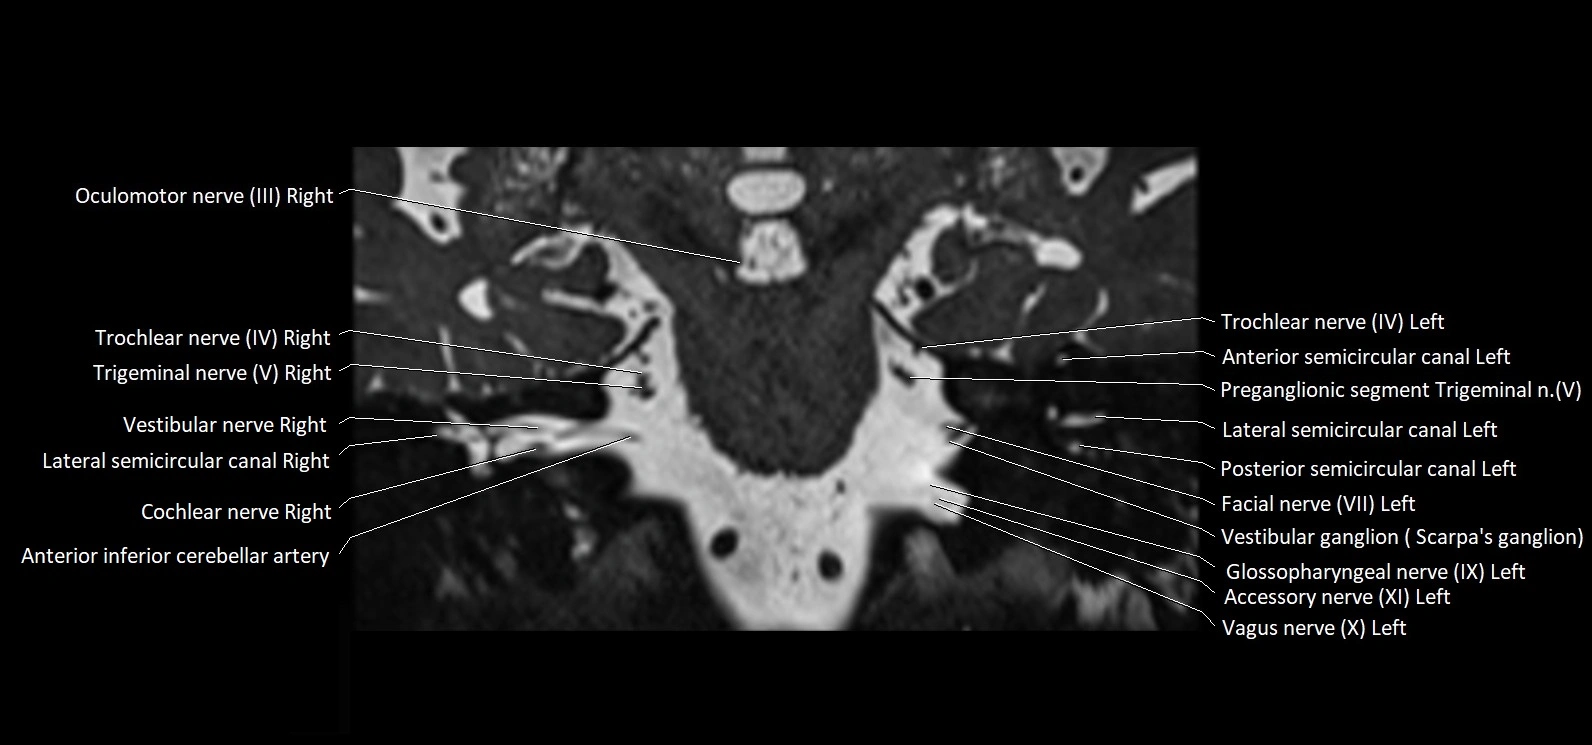

MRI Appearance

• The abducens nerve is a small, thin, linear structure

• Best visualized on high-resolution T2-weighted 3D MRI sequences (e.g., FIESTA or CISS)

• Seen as a hypointense (dark) line running from the brainstem at the pontomedullary junction, traversing the prepontine cistern, and entering Dorello’s canal under the petrosphenoidal ligament, then into the cavernous sinus, and finally the orbit

• May be challenging to visualize in standard MRI due to its small size

• Pathology may be inferred by absence, displacement, or enhancement of the nerve